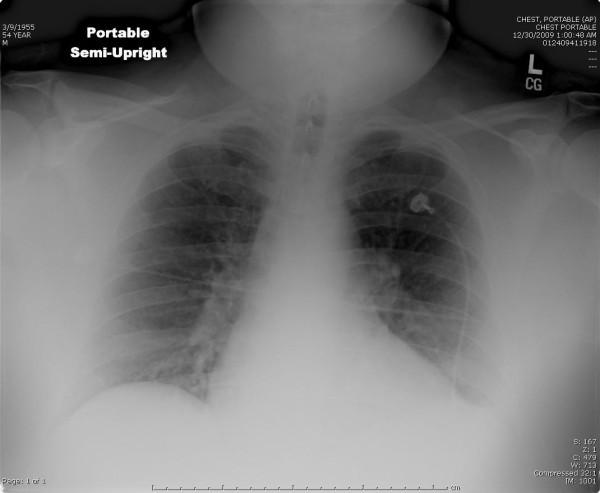

We present a case report of a 54 year old man with respiratory distress and chest pain as the initial Emergency Department presentation of a perforated duodenal ulcer.

We discuss an unusual presentation of a perforated duodenal ulcer that was recognized in the emergency department and treated promptly. The patient was surgically treated immediately, had a prolonged and complicated post-operative course, but is ultimately doing well. We also provide a brief literature review of the risk factors, imaging choices, and management decision required to treat a perforated ulcer.